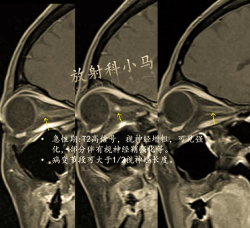

视神经炎

视神经炎是视神经的炎症。当它影响双眼时,动物突然失明,瞳孔扩张,一动不动。兽医将通过检眼镜检查马的眼睛、进行视觉反射测试和完成神经学检查来诊断这种情况。此外,血液检查、x光检查和其他检查也可能是确定病因所必需的。视神经炎可由病毒、真菌、原生动物或寄生虫感染引起;毒物;创伤;以及其他原因。治疗旨在管理潜在的疾病,通常包括使用药物来减少炎症和损伤。